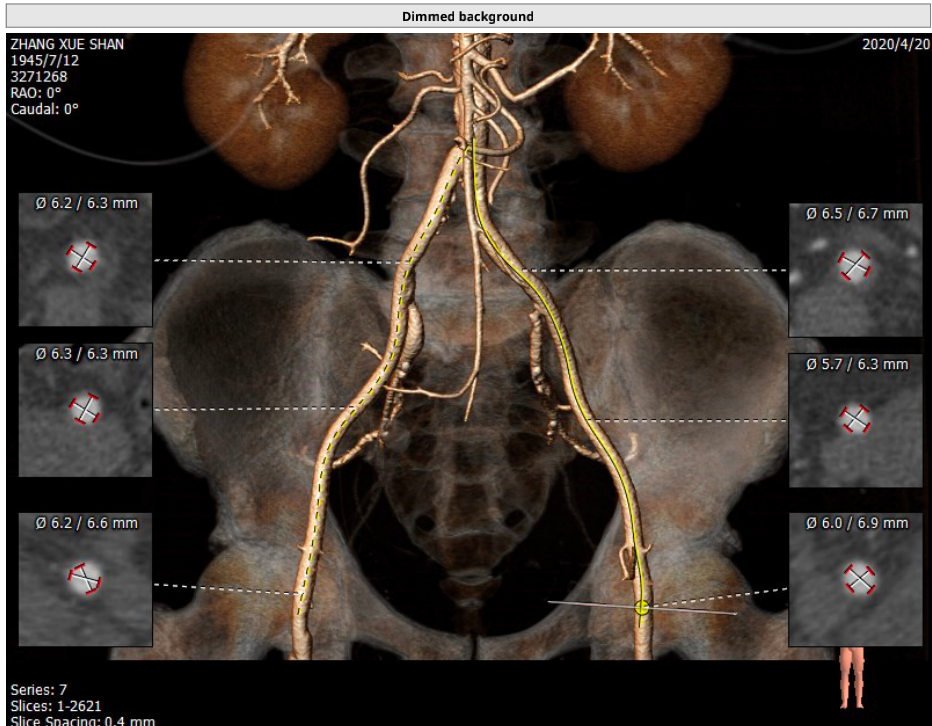

血管入路解剖: